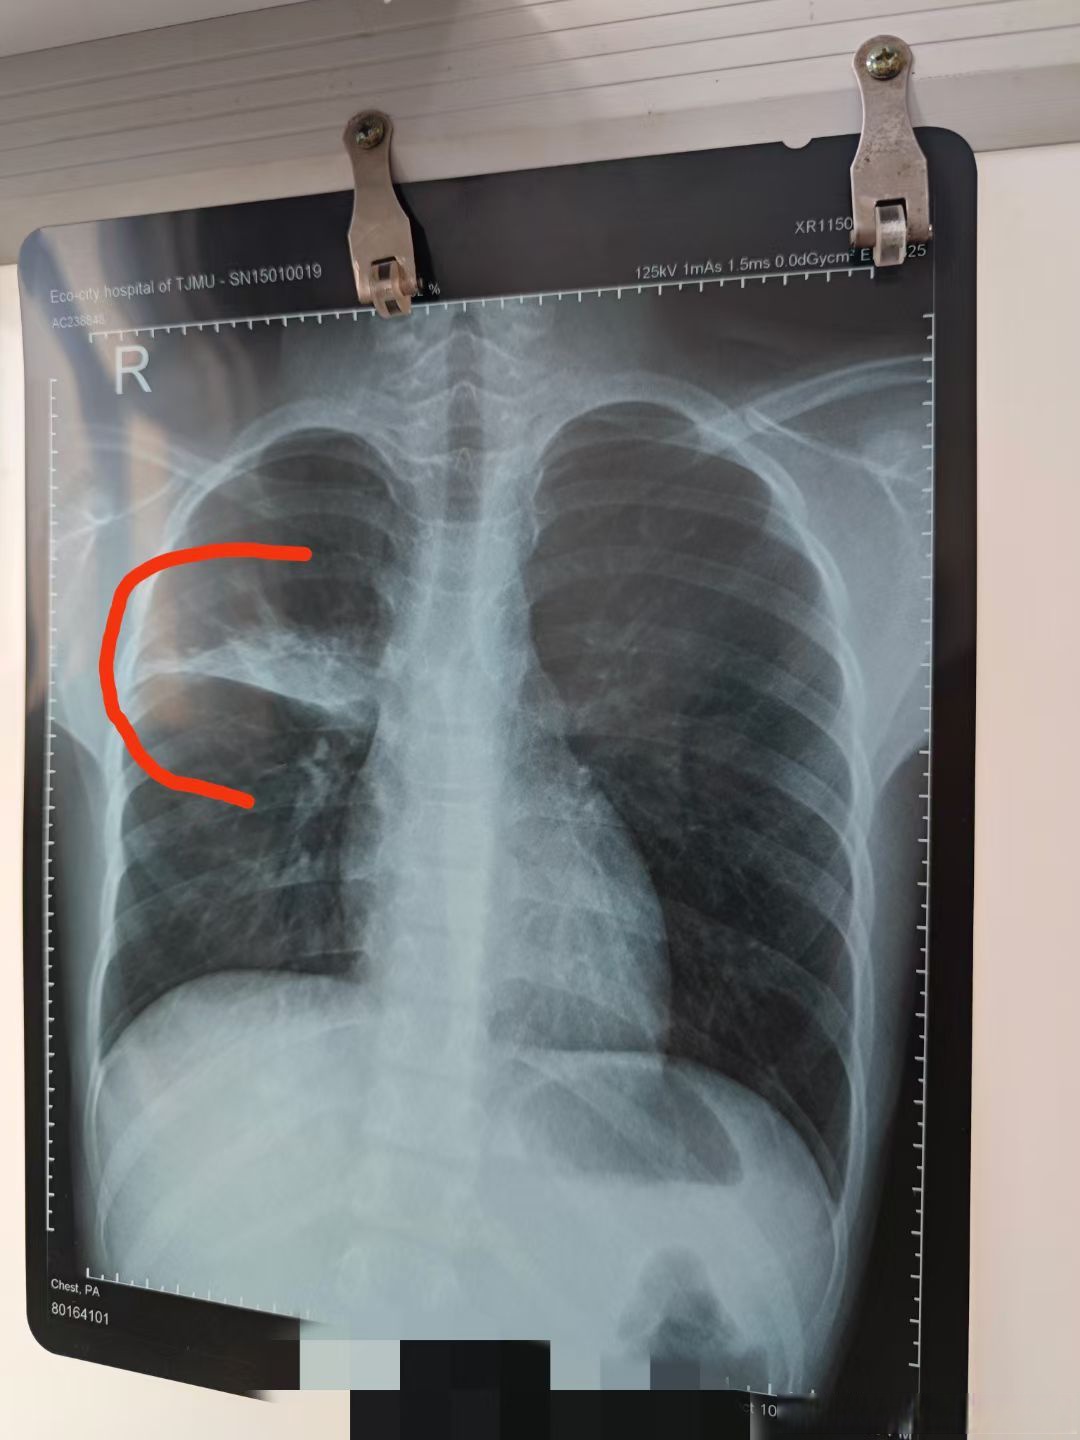

什么是双肺纹理增强?

双肺纹理增强并非独立疾病,而是肺部影像学检查中的一种表现,可能由肺炎肺结核肺纤维化等疾病导致,需根据病因进行针对性治疗肺炎在肺炎早期,肺组织发生炎症反应,可导致双肺纹理增强患者需避免过度活动,适当增加饮水量以促进代谢...